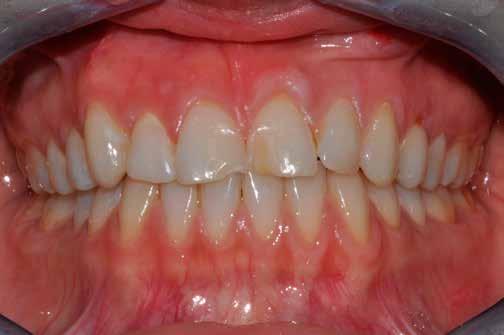

Hölgy páciensem az első konzultáció során tipikus kórtörténetet vázolt fel: Gyermekkora óta szeretett volna fogszabályozó készüléket, hiszen mindig is zavarta a class 2-es eltérésnél tipikusan jellemző nagy overjet (1-3. képek), és természetesen az ezáltal kifelé álló felső metszőfogai, részben a felső metszők protrúziója, részben pedig a disztálisan elhelyezkedő mandibula miatt. Annak ellenére, hogy több fogszabályozó szakorvosnál is járt az évek során, de mivel saggitális eltérése és az alsó metszőfogak torlódása miatt négy kisőrlőfog extrakcióját, illetve emellett sokszor állcsont műtétet is javasoltak neki, nem vágott bele a kezelésbe (4-5. képek).

A fogorvosa – nagyon helyesen – felhívta a figyelmét, hogy parodontális státusza is valószínűsíthetően romlani fog az eltérése miatt, újabb kört futott, immár 39 évesen, de még mindig premoláris fogak húzása és állcsontműtét nélkül szerette volna a fogszabályozást.

A konzultáció során arról is beszéltünk – ahogy az ilyenkor lenni szokott –, sohasem szeretett igazán mosolyogni, de a Pitts Protokolloknak köszönhetően az arc- és mosolyesztétikai céloknak megfelelően kerül megvalósításra az okklúziós korrekció. Az okklúziós kezelési célok az alábbiak voltak: a felső és alsó fogív nivellálása és tágítása, az alsó fogsor/ mandibula mezializálása, valamint a harapás megemelése által a mélyharapás rendezése.

A fogkontúrálás és az interproximális redukció alkalmazásával a mikroesztétikai részletek tökéletesítése is megtörtént (11. kép) A kezelés mindössze 16 hónapig tartott, megtörtént a rágófunkció helyreállítása, és az esztétikai végeredmény sokéves várakozás után valóban fordulópontot jelentett páciensünk életében (12-14. képek).